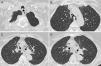

Bronchoscopic images. Panel A: Invagination of tracheal posterior wall membrane during spontaneous breathing in the studied patient with narrowing of tracheal lumen. Panel B: Positioning of endoluminal y silicon stent (Dumon type) in trachea of the studied patient. Panels C and D: Fully covered metal stent (Leufen) placed in trachea of the studied patient.

In December 2007 JAT underwent endoscopic laser treatment with poor results and in September 2008 an endoluminal silicone y-stent (Dumon type) was inserted (Fig. 1B), but it was not successful probably because of the migration of the obstruction point toward the periphery of the airways tree.3,5

The following December it was replaced by a fully covered metal stent (Leufen) (Fig. 1C and D), which was removed in February 2009 because of granulation tissue growth and viscous secretion.